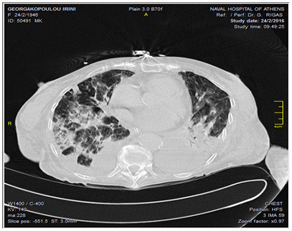

A 70 year old woman admitted to the hospital complaining for dyspnea and low foot edema for the last 15 days. From her history she was diagnosed since Nov 2011 for bullous pemphigoid syndrome and was under medication with prednisolone. When she arrived she was hypoxemic (P1) that corrected with the use of oxygen at 2 lt. renal cannula. The rest of the tests were normal except the lung CT-scan that was a picture of interstitial pulmonary fibrosis (P2). There was a similar picture during 9/15 that was talking about signs of COPD and pneumonic hypertension as well.

Most of the patients survive the initial acute event, with a very low rate of in-hospital mortality or complications. Even when ventricular systolic function is heavily compromised at presentation, it typically improves within the first few days and normalises within the first two months.13,14 It is not likely for the same recovered patient to experience the syndrome twice. The average ages at on set are between 58 to 75 years affecting between 1.2% and 2.2% of people in Japan and 2% to 3% in western countries (Figures 1–4).

Figure 2 P2 CT scan.